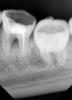

diesel87 Опубликовано 3 декабря, 2012 Поделиться Опубликовано 3 декабря, 2012 Вечер добрый, сегодня была пациентка, 36, 46 в обострение Pt обе, сделали снимки. это 46, тут разряжение по бифуркации, планирую на удаление это 36, не могу понять, есть ли тут тоже самое с бифуркацией, начал пытаться распломбировывать и проходить туда куда до меня не прошли, к сожалению времени оставалось всего минут 30 поэтому дошел только так, послезавтра отвели достаточно времени, попробуем пройти. Ссылка на комментарий

FBR Опубликовано 4 декабря, 2012 Поделиться Опубликовано 4 декабря, 2012 Вечер добрый, сегодня была пациентка, 36, 46 в обострение Pt обе, сделали снимки. это 46, тут разряжение по бифуркации, планирую на удаление это 36, не могу понять, есть ли тут тоже самое с бифуркацией, начал пытаться распломбировывать и проходить туда куда до меня не прошли, к сожалению времени оставалось всего минут 30 поэтому дошел только так, послезавтра отвели достаточно времени, попробуем пройти.Оба с пляжа... 1 Ссылка на комментарий

stomlg Опубликовано 4 декабря, 2012 Поделиться Опубликовано 4 декабря, 2012 стремные =) почему то тоже подумал о перфе в 36... Ссылка на комментарий

diesel87 Опубликовано 4 декабря, 2012 Автор Поделиться Опубликовано 4 декабря, 2012 стремные =) почему то тоже подумал о перфе в 36...что стремные? Возможно эту перфу закрыли давно, дно твердое, но разряжение по бифуркации имеется... Ссылка на комментарий

ElenDent Опубликовано 4 декабря, 2012 Поделиться Опубликовано 4 декабря, 2012 Я не понял, а что с фуркацией у 36 при зондировании? Там такое впечатление, что копнешь экскаватором и провалишься. И неужто кармана нет? Ссылка на комментарий